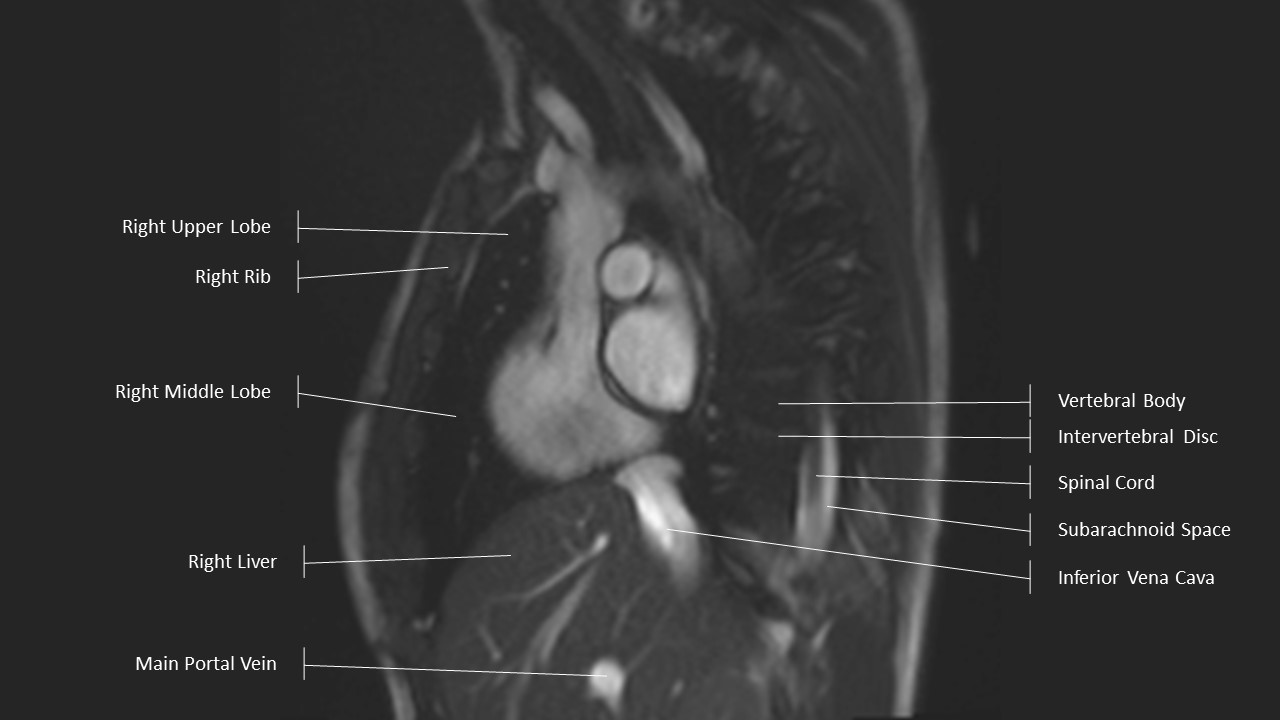

Aortic Arch Series